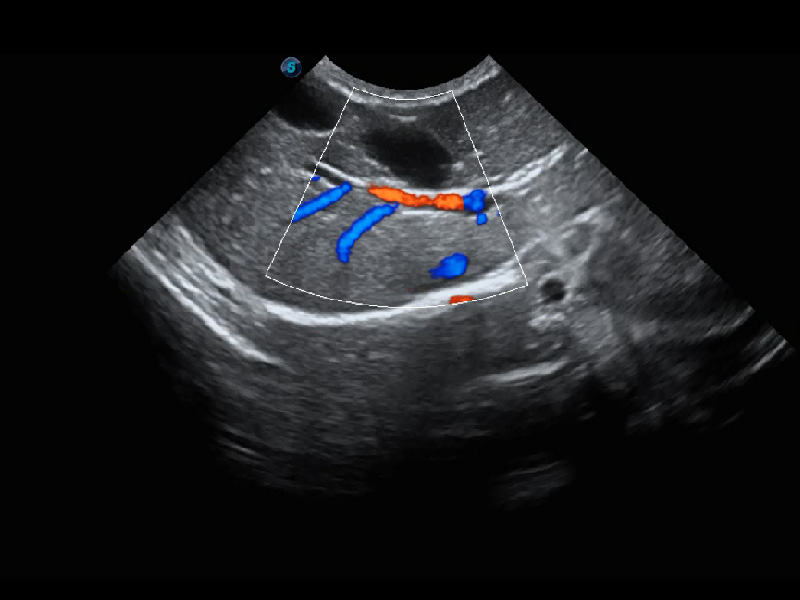

优异的基础图像

(犬)肾脏血流